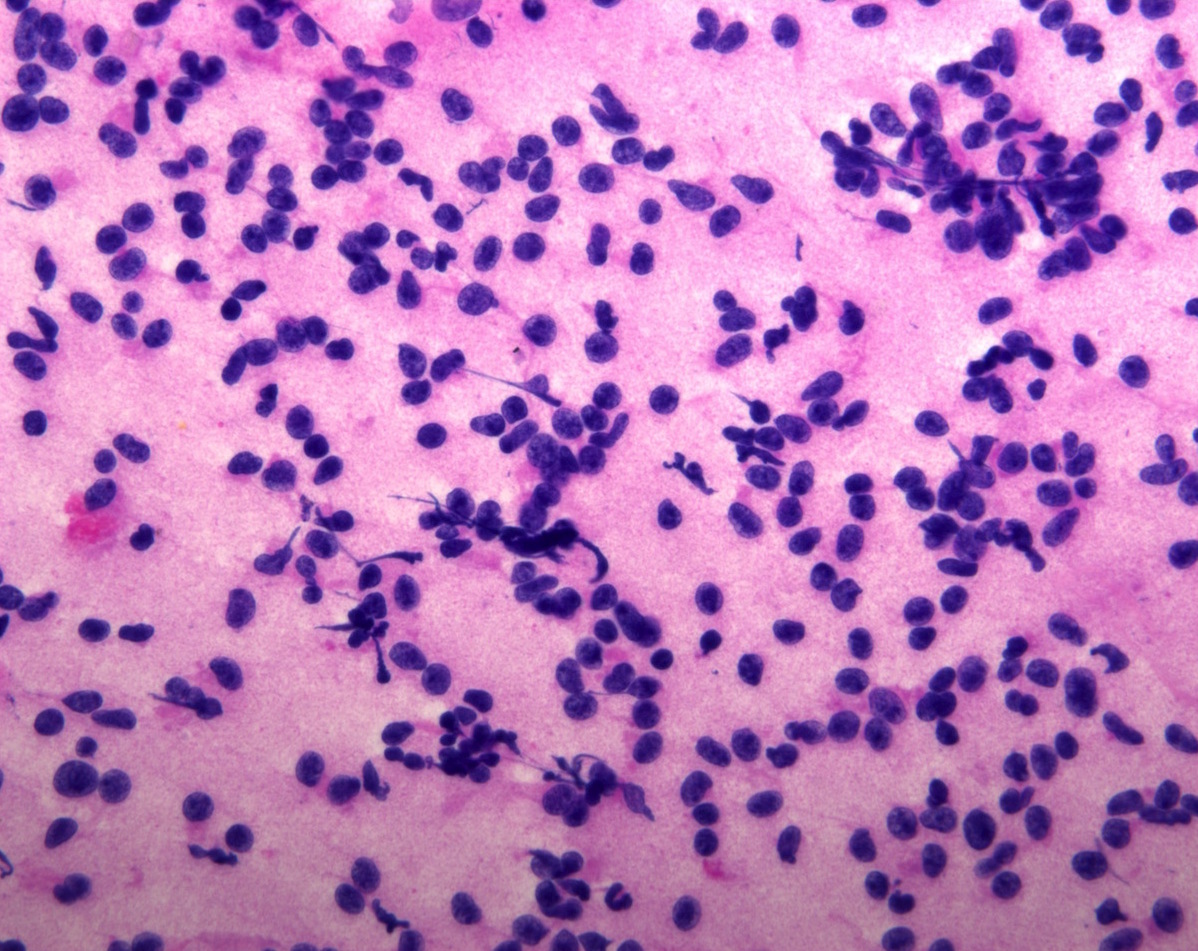

Frozen section description

- Frozen sections are discouraged

- Most cases do not require intraoperative consultation but in unusual situations (e.g., where the differential diagnosis is inflammation), touch preps can be used for cytologic assessment without compromising residual tissue that is retained for proper immunohistochemical analysis

Cytology description

- Normal pituitary has mixed cell types on smear preparation whereas tumors show uniform morphology and cell type

- Tumors produce cellular smear with discohesive small round blue cells

- Some tumors have specific cytologic atypia (e.g., fibrous bodies of sparsely granulated somatotroph tumors, Crooke hyaline of Crooke cell tumors)

Cytology images